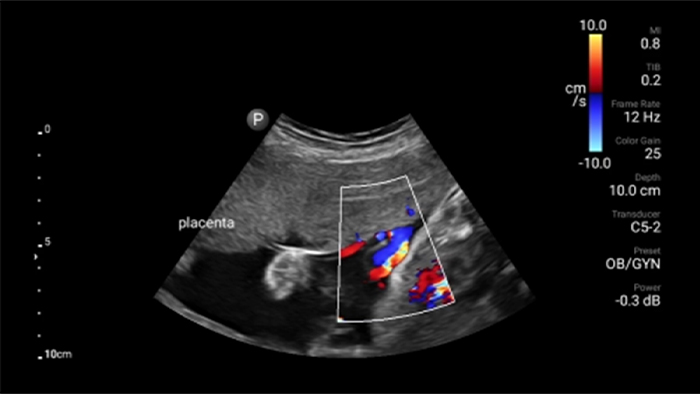

Exceptional ultrasound imaging

Lumify handheld ultrasound offers images that enhance diagnostic confidence.

See more when it counts

Lumify can help you make real-time decisions with more confidence, from assessment to recovery. Reveal the subtle details of an image, uncover enriched tissue definition with multiple angles and much more.